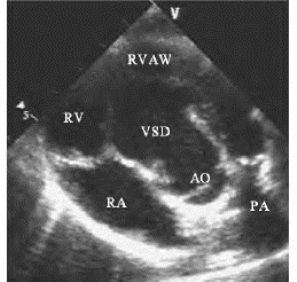

图17-1 法洛四联症二维及彩色多普勒图(见彩图25)

左图:左心室长轴切面,显示主动脉骑跨、室间隔缺损、右室壁及室间隔增厚;右图:彩色多普勒,显示右室向主动脉的蓝色分流束

(1)主动脉骑跨:左心室长轴及五腔切面,显示主动脉内径增宽,前壁与室间隔连续中断,并向右前移位,骑跨于室间隔之上(图17-1左图),骑跨率大多数在60.0%以下;左心室长轴切面显示主动脉瓣与二尖瓣前瓣之间仍为纤维连续。有作者认为若主动脉骑跨超过90.0%,可称为法洛四联症型右室双出口。法洛四联症型右室双出口在大血管短轴切面,仍显示右室流出道及肺动脉环绕主动脉短轴的图像。骑跨程度可按下式计算。

(2)室间隔缺损:左心室长轴及五腔等切面,显示主动脉前壁与室间隔连续中断(图17-1左图)。多数为较大的嵴下型缺损,直径一般在1.5~3.0cm,大血管短轴切面,相当于时钟9:30至12:00位置;肺动脉瓣下缺损较少见,大血管短轴切面相当于时钟12:00至2:00位置(与肺动脉瓣位置有关),缺损上缘达肺动脉环部,此型常不显示室上嵴结构。

①右室向主动脉分流:于胸骨旁左心室长轴,显示收缩中晚期由右室向主动脉的蓝色分流束(图17-1右图),或于胸骨旁及心尖五腔切面,显示左、右心室的蓝色血流束在主动脉根部汇合。